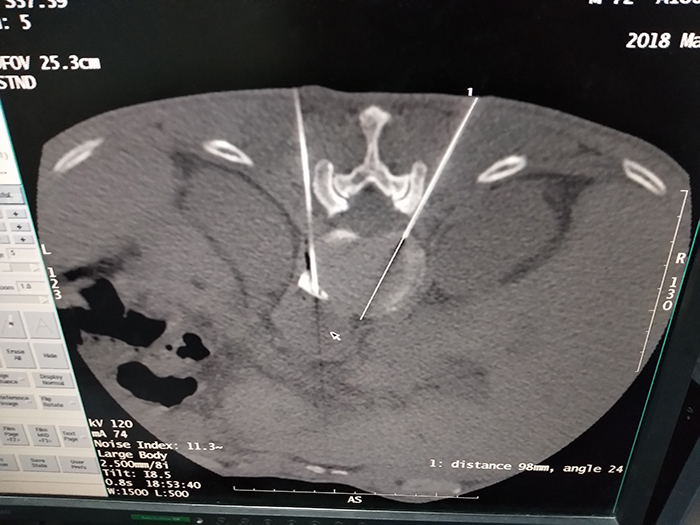

3月22日下午,疼痛麻醉门诊联合CT科、普外一科,为病人实施了腹腔神经丛毁损术。手术采用局部麻醉,在CT引导下准确穿刺腹腔神经丛进行神经毁损手术治疗,整个手术过程历经45分钟,患者无不适,自感疼痛完全缓解,术后患者安全返回病房。第二天上午,李卫东主任查房,患者主诉无任何疼痛感觉,睡眠良好,并露出了久违的笑容,并于术后第三天满意出院!

此项技术主要运用于癌痛的患者或者一些复杂的内脏神经疼痛又无法行手术处理的患者。腹腔神经丛解剖位置位于胸腰段椎体前方、接近腹主动脉及下腔静脉,手术操作风险较大,对穿刺要求极高。